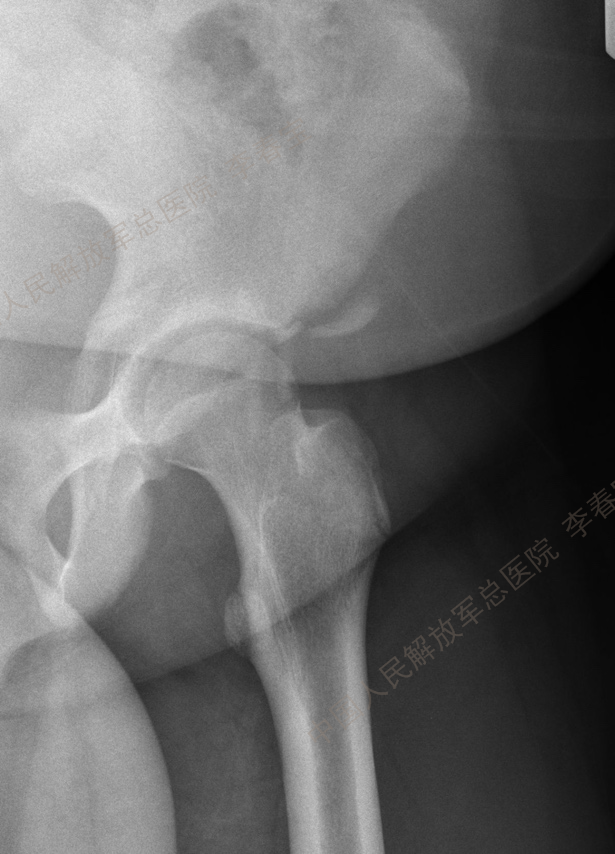

2. 髋关节撞击症

髋关节撞击征(femoroacetabular impingement, FAI)是引起中青年,特别是运动量较大者髋关节疼痛的主要原因,也是引起早期骨关节炎的重要因素。按受累解剖部位形态学改变,FAI 可分为:(1)凸轮型撞击(cam impingement);(2)钳夹型撞击(pincer impingement);(3)凸轮钳夹混合型撞击(mixed type)。该病好发于喜欢运动的青壮年,患者常有不明原因的髋关节慢性疼痛,以腹股沟区最为多见,也可出现股骨后侧和外侧疼痛,同时伴有髋关节活动受限,以屈曲内旋受限最为显著。通过髋部X片(包括骨盆正位X线片、髋关节穿桌侧位、蛙式侧位X线片、屈髋侧位片或假斜位片)、MRI和CT检查一般不难诊断。一般经休息、限制髋关节运动、服用非甾体抗炎药以及封闭治疗等保守治疗无效可考虑手术治疗。治疗方面,早期主要是通过股骨头脱位技术进行开放手术治疗,目前的主流是通过髋关节镜微创技术进行治疗,包括镜下清理凸轮畸形,恢复股骨头颈区的自然弧度;清除髋臼边缘的骨赘和适当磨除髋臼周围影响髋关节活动的骨质,以减少髋臼前方的过度覆盖,最后把髋臼盂唇剩余部分缝合固定在骨面或髋臼缘上。